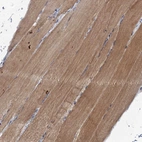

Immunohistochemical staining of human skeletal muscle shows moderate cytoplasmic positivity in myocytes.